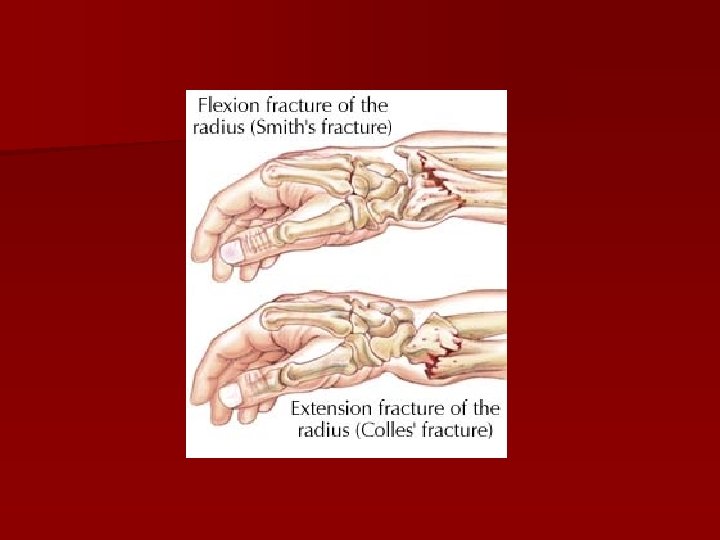

Fracturi extraarticulare (supraarticulare) n Fractura Pouteau – Colles n Fractura Goyrand – Smith (Pouteau – Colles inversată)

Fractura Pouteau - Colles Fragmentul distal se deplasează : Posterior (---> deformarea în dos de furculiţă) n Proximal (---> angrenarea fragmentelor) n Radial (---> mâna în baionetă) n Tasarea posterioară a fragmentelor

Fractura Pouteau - Colles Diformitate în “dos de furculiţă”

Fractura Goyrand – Smith Diformitate în “faţă de furculiţă”